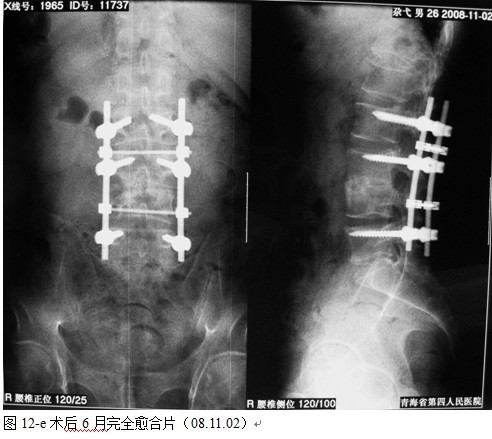

本组手术用时间3~4h , 平均3.5h 。术中出血300~500ml , 平均约350ml 。术后症状完全缓解,无神经功能障碍加重等并发症,1例营养差的老年患者伤口出现窦道,1例因肝功能差,术后未口服抗痨药,伤口出现窦道,经换药后二期愈合,其余病例伤口均一期愈合。马尾神经受损的患者术后基本恢复正常。术后一周后凸角平均 5.4°后凸畸形平均矫正90%以上, 最终后凸角平均8.3°,后凸角度平均丢失4.2°。随访3个月有87%(40/46)有骨痂形成,6个月91.3%(42/46)明显骨性愈合(见图),其余4例9-12个月内愈合,随访时间3-32个月,平均11个月,46例患者中2例在术后2个月和3个月时背部形成脓肿,换药后治愈。2例出院1月后并发结核性脑膜炎,治疗后好转。1例因椎弓根钉偏外,刺激神经根,5个月后从侧方脱出,疼痛加重,因前后路植骨完全愈合,取出后症状完全缓解。

中国学者金大地[22]等采用一期前路病灶清除植骨前路钢板固定治疗腰椎结核,平均18°的后凸畸形得以矫正,Mukhtar[23] AM等采用前路病灶清除植骨分期或同期后路固定治疗腰椎结核22例,术后后凸畸形矫正度数平均为27°。从我们的随访结果看,术后后凸畸形平均矫正度数为26.9°,后凸畸形平均矫正90%以上, 6个月-49个月后随访,后凸角度平均丢失4.2°。本术式也适用于结核所引起的弹性差的后凸畸形,对于病灶纤维化或骨化的非弹性后凸畸形,后路固定后,先行前路病灶、纤维化或骨化切除、松解,逐步刮除病灶、逐步撑开,达到畸形矫正和植骨的目的。